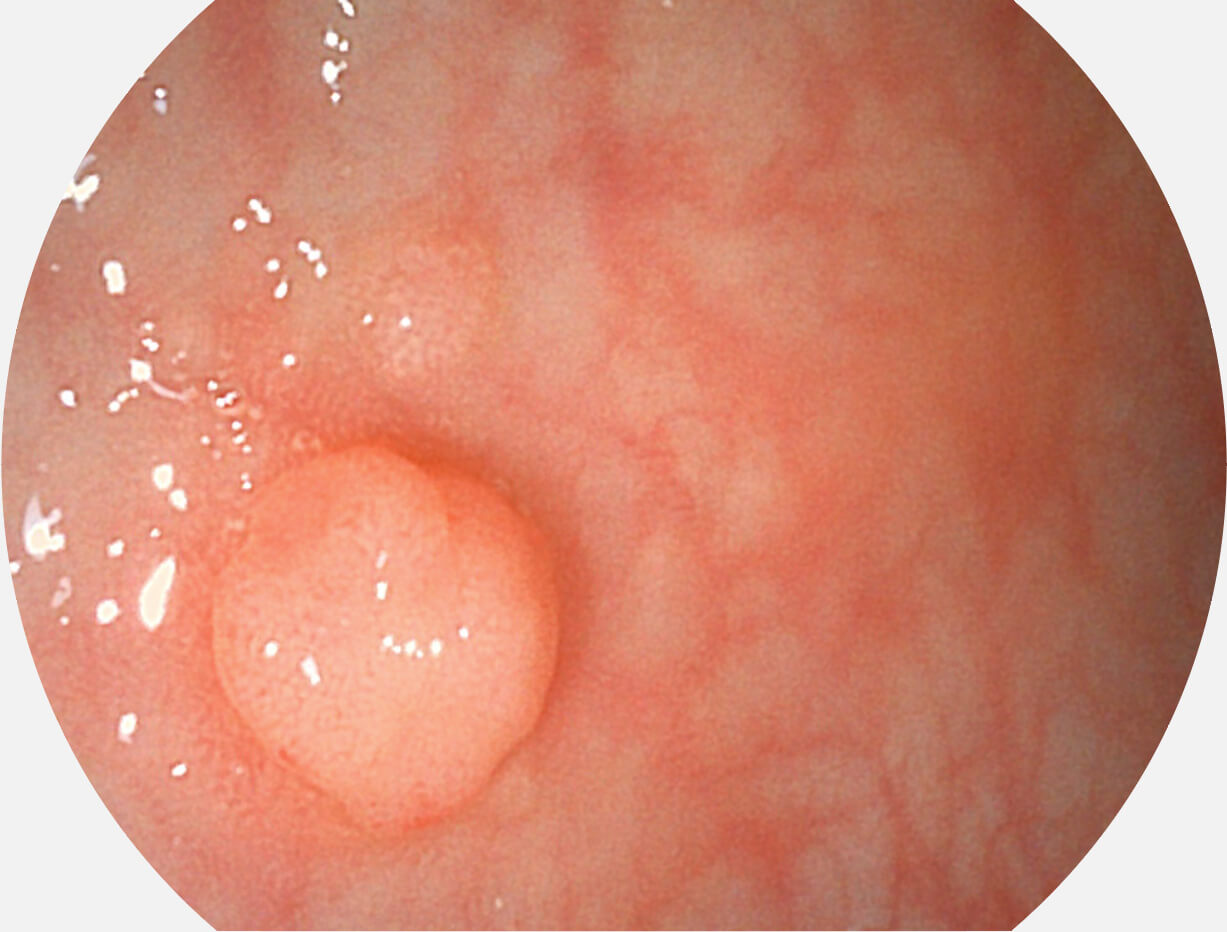

图像具有高亮度、高黏膜血管颜色对比度的特点,且不改变粘液、食物残渣、粪便的基本颜色,可在中远景下进行观察,助力消化道早期疾病的诊断。

• 白光图像 SFI图像